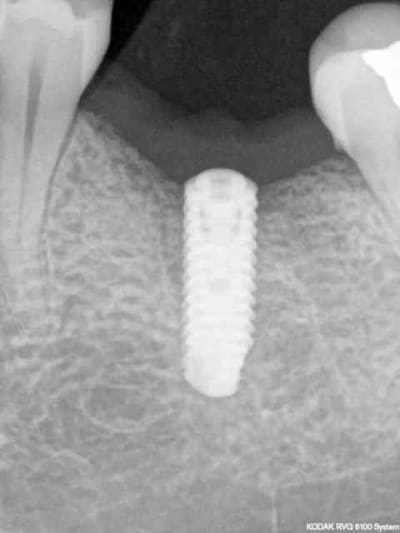

comme ce petit cas

la 2ème radio est prise 18 mois après la 1ère

PS pour Gulguch c'est bien un implant de 6 mm de diamètre en distal et pourtant pas la moindre perte osseuse...